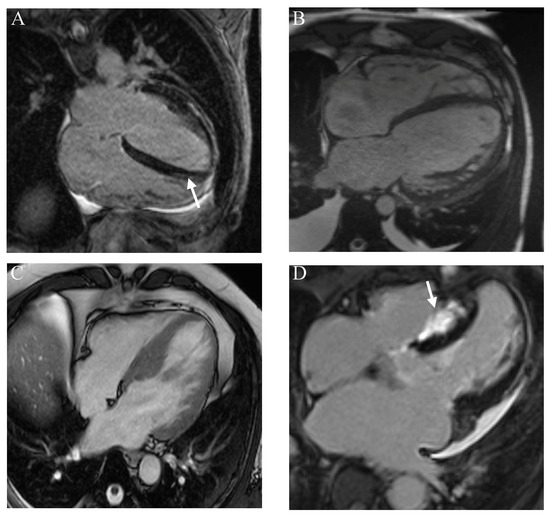

心脏结节病的影像学表现

本文作者筛选了66项以遗传学和结节病为重点的文献进行了综述研究,揭示了结节病与遗传学的深层联系。作者发现,心脏结节病的诊断往往十分困难,需要借助先进影像手段辅助检查。而在遗传层面,特定基因(如 HLA、BTNL2、TNF-α)与疾病发生密切相关,尤其在非裔人群和家族聚集病例中更为突出。这些发现不仅解释了不同患者间的差异性,也为未来的基因筛查和精准干预提供了科学依据。